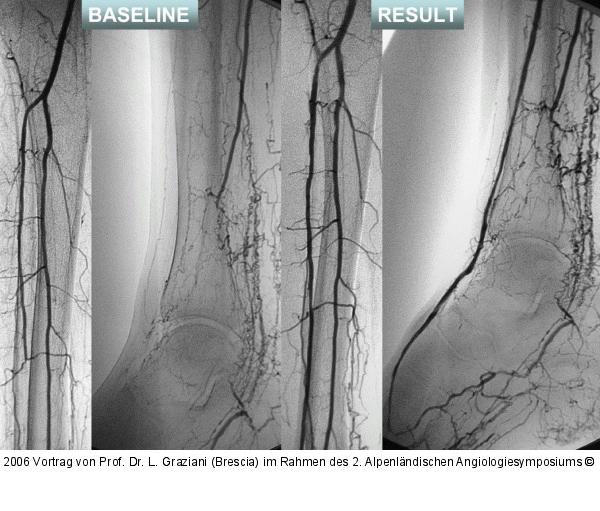

Vortrag von Prof. Dr. L. Graziani (Brescia) im Rahmen des 2. Alpenländischen Angiologiesymposiums

PTA of the foot arteries in diabetics: Extremities Extreme Angioplasty

Abbildung 17: Revaskularisation